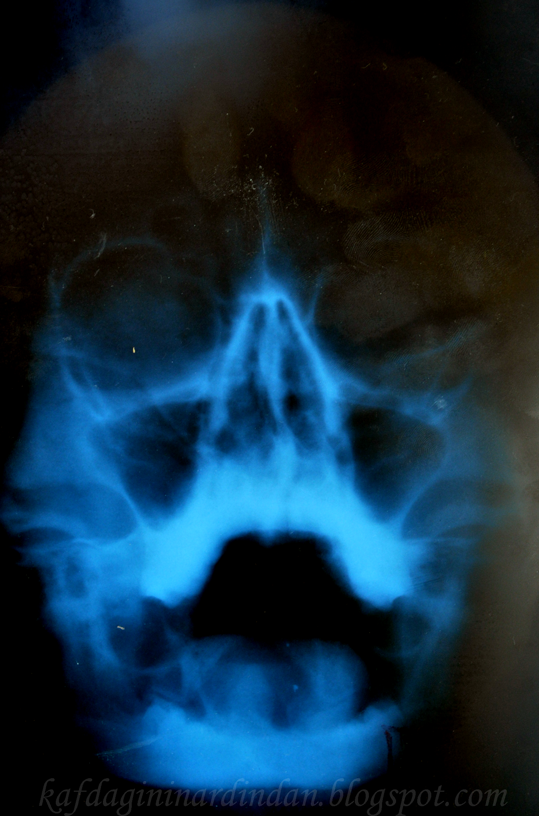

Bu film çekilirken ağzınızı mümkün olduğu kadar açıp röntgen aletine dayıyorsun. Sonra da tabii benim gibi gülme krizine giriyorsun:)) Sinüzitten şüphelenen doktor bu filmi istemişti ama insan kendi kafatasını görünce, üstelik de böyle ağzı açık bir şekilde, bir tuhaf oluyor!

İşte bu da blogcuğuma eklediğim ilk fotoğrafım olsun:)) "Bak bak hahahah" derken üzerinde çok parmak izi bırakmışım kusura bakmayın:P Utanmadan bloga kafa röntgenimi koymuşum, birkaç parmak izinin lafı olmaz değil mi!

İyileştim baya, azaldı öksürüğüm. Filmde de sinüzit görünmüyormuş saten:)) Teşekkür ederim;)